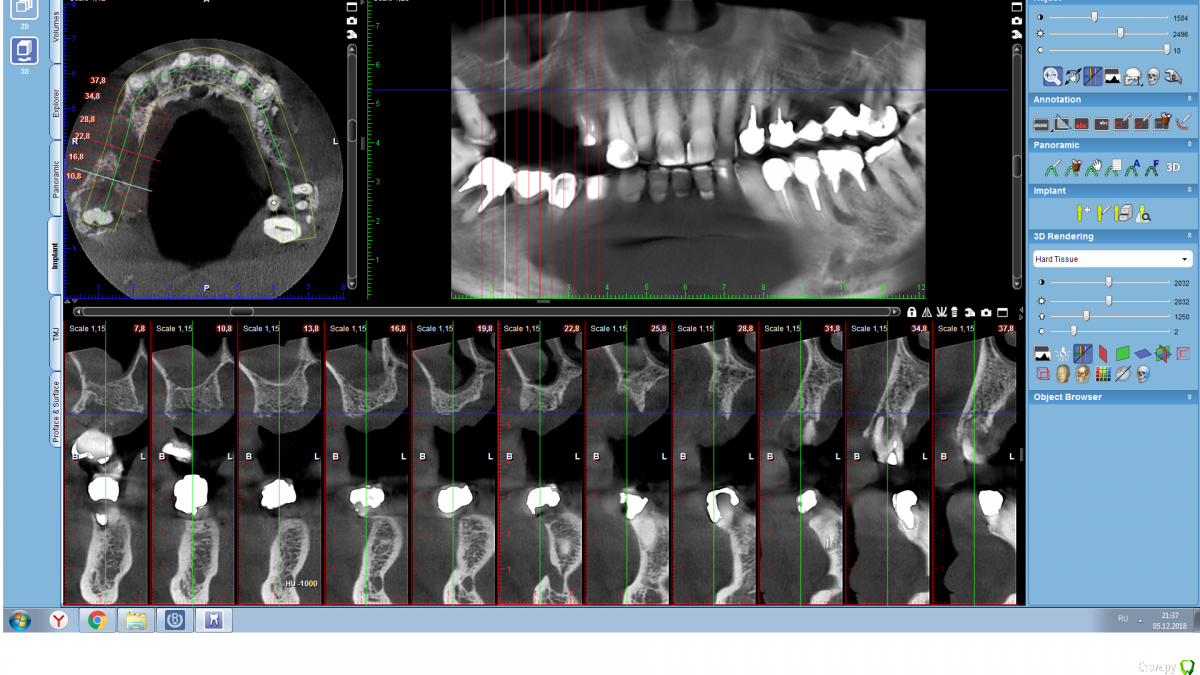

Serg2018 Опубликовано 28 ноября, 2018 Автор Поделиться Опубликовано 28 ноября, 2018 Вот пытаюсь выложить несколько срезов КТ правой стороны, надеюсь, я это правильно понял, делаю впервые. Также тыкал мышкой и она мне что-то замеряла, если в мм, то получается, что в самой тонкой части толщина 2,8 мм? или это я все неправильно понимаю? Ссылка на комментарий

Nazim_NV86 Опубликовано 28 ноября, 2018 Поделиться Опубликовано 28 ноября, 2018 (изменено) Sirona Galileos ?Должно быть окно, где срезы видны как распил. Сечение. Лучше на этом измерять. Можете всю томограмму загрузить на яндекс диск и выложить ссылку. Но сначала проверьте как работает запуск. На той программе, что выше написал, запуск скорее всего возможен только с диска. Если среди файлов на диске есть файл DCM, то его одного достаточно. Просмотрщик не нужно выкладывать. Изменено 28 ноября, 2018 пользователем Nazim_NV86 Ссылка на комментарий

Serg2018 Опубликовано 4 декабря, 2018 Автор Поделиться Опубликовано 4 декабря, 2018 (изменено) Психическое равновесие восстановил и опять записался на консультацию к хирургам. Сегодня сходил в сетевую клинику эконом уровня. Доктор нормальный (как и предыдущий). После этого визита решил больше никуда не ходить, картинка сложилась, что делать, приблизительно ясно. Они там для бесплатной консультации делают панорамный снимок бесплатно. Снимок выглядит лучше, чем мой апрельский. Посмотрел также КТ и визуально. Вывод- у меня пограничная ситуация, можно синус лифтинг делать, можно нет. Из новой инфо- у меня аномально широкая кость, что хорошо для коротких имплантов. Костную пластику справа можно сделать, но надеяться, что нарастится 7 мм необходимых мне для красоты, не стоит. Скорее получится плюс 2 мм. Альфа Био у них вообще 7500 и доктор говорит, что разница в приживляемости по сравнению с другими марками не более чем 2-3%, т е теоретическая. Решил- неделю подумаю о костной пластике. На красоту мне практически наплевать, у меня и коронки были длинные. А вот то, что пластика позволит уменьшить шансы на синус лифтинг, это интересует, конечно. Если решусь делать пластику, то сначала делают пластику справа, потом ждем. Потом снимаем мостик слева, вырываем все ненужное, ждем, делаем протез на обе стороны с перемычкой по небу. Гуляем неск месцев. Делаем КТ и окончательно решаем по синус лифтингу и характеру имплантов. Вопрос- а костная пластика это травматичная операция? Это как зуб удалить - день покровит, образуется сгусток и через неделю все заживет? Или пить антибиотики, отек на поллица на две недели и месяц боли?Спасибо. Изменено 4 декабря, 2018 пользователем Serg2018 Ссылка на комментарий

Serg2018 Опубликовано 4 декабря, 2018 Автор Поделиться Опубликовано 4 декабря, 2018 (изменено) Поговорил с доктором, которого я посещал еще ранее, но он не смог открыть нормально КТ. Я ему послал картинку подготовленную Nazim (еще раз большое спасибо). Доктор сказал, картинка ясная, никакой трансплантации кости или еще чего не надо, объем кости достаточный для коротких имплантов. Вырывайте все лишнее, делайте протез, через два месяца новое КТ и импланты. Так и буду действовать. Утолщение тканей пазухи он тоже видит (я вообще не пойму где там пазуха, ну оно мне и не надо). Изменено 4 декабря, 2018 пользователем Serg2018 Ссылка на комментарий